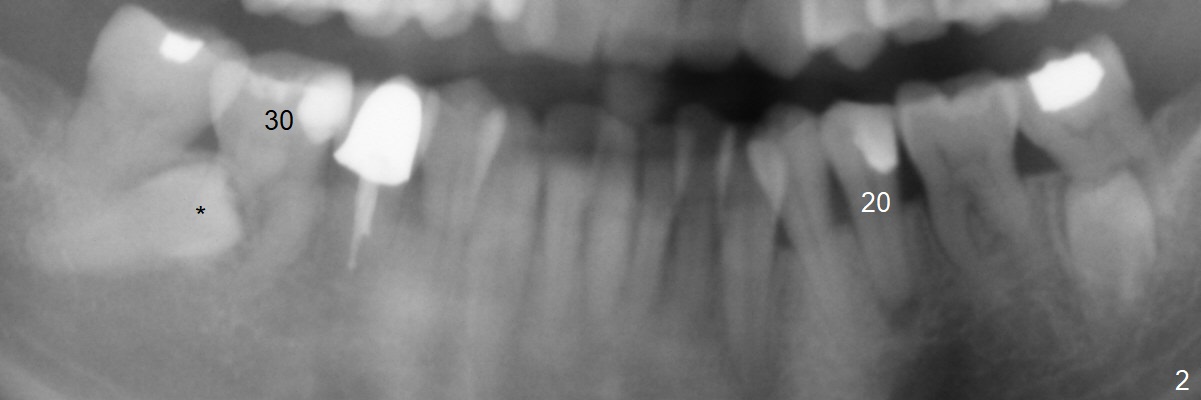

A 45-year-old woman with severe crowding (Fig.2) presented to my office 9 years ago; the tooth #18 appears to have root resorption, most likely due to a supernumerary tooth (Fig.1 *).  The latter seems to be erupting in 6 and 9 years (Fig.2,3), probably because of immature apex (Fig.2, as compared to the supernumerary tooth in the lower right (*)).  Recently the patient has transient sensitivity at #18.  The tooth has mobility I without deep periodontal pockets.  If the tooth #18 turns to be non-salvageable, what should be done?  The tooth #20 has received root canal therapy, while the tooth #29 has had RCT retreat.